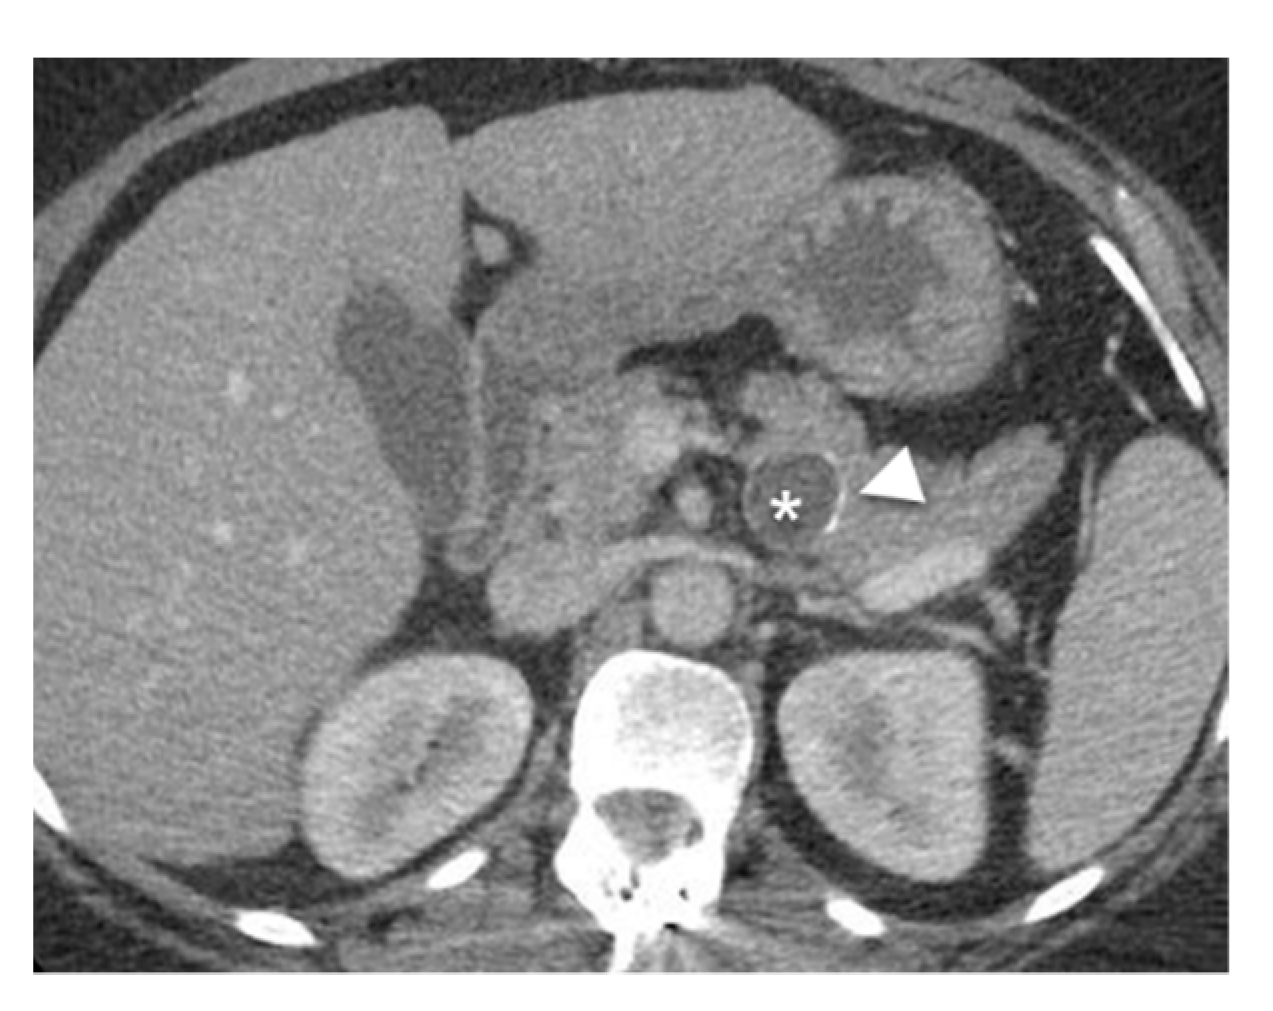

- Mamone, G.; Barresi, L.; Tropea, A.; Di Piazza, A.; Miraglia, R. MRI of mucinous pancreatic cystic lesions: A new updated morphological approach for the differential diagnosis. Updates Surg. 2020, 72, 617–637. [Google Scholar] [CrossRef] [PubMed]

- Tirkes, T.; Aisen, A.M.; Cramer, H.M.; Zyromski, N.J.; Sandrasegaran, K.; Akisik, F. Cystic neoplasms of the pancreas; findings on magnetic resonance imaging with pathological, surgical, and clinical correlation. Abdom. Imaging 2014, 39, 1088–1101. [Google Scholar] [CrossRef] [PubMed]